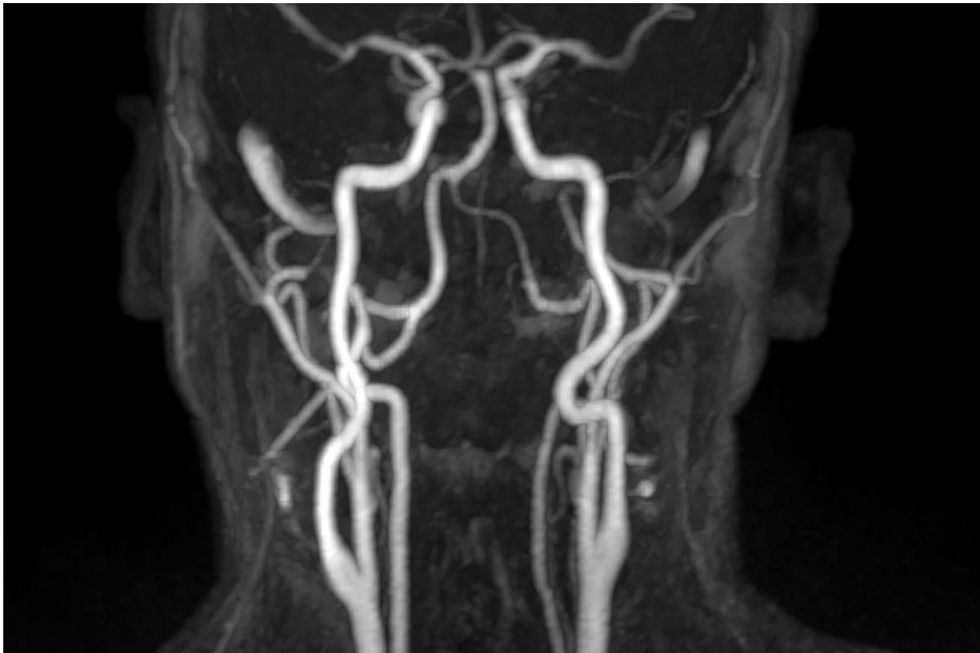

“Higher circulating calcium levels within the normal range are associated with increased thickness in the major arteries going to your brain and a higher prevalence of abdominal aortic calcification, and more calcified plaques in the coronary arteries,” she said.